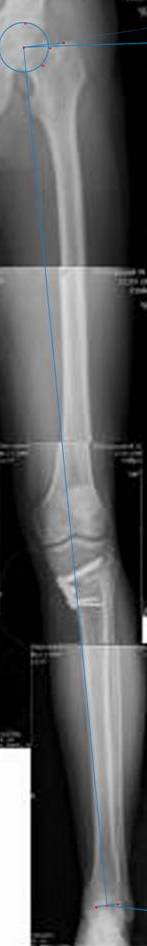

картинки оперированного пациента 40 лет, травма в 2006 году.

оперирован 06.11.2009г - корригирующая остеотомия большеберцовой кости.

Я картинку собрал с некоторыми погрешностями, если провести отвес от центра вращения головки бедра до середины голени (на пациенте),то имеется небольшой вальгус (гиперкоррекция)конечно она (гиперкоррекция) не достигает 10 гр, но 5 гр она достигает.

К сожалению, не очень удачный пример. Если верить Р-граммам, имеет место быть дисплазия мыщелков бедренной кости с наклоном суставной линии. Это уже создает сложности получения хороших отдаленных результатов. Кроме того, по классике, необходима гиперкоррекция с созданием вальгуса 7-10 градусов для максимальной разгрузки медиального отдела КС. Если верить укладке, то линия сустава имеет четкий варусный наклон, поэтому результат операции м.б. кратковременным. В этих случаях показана двойная остеотомия бедра и тибии.

Если сделать правильно, то видно, что бедренная кость в порядке, а цель остеотомии (низкой, кстати), не достигнута вовсе.

Сохраняется варус. Для того, чтобы создать вальгусную гиперкоррекцию, не моделируя при этом откровенный Х голени, можно сделать медиализирующую остеотомию.